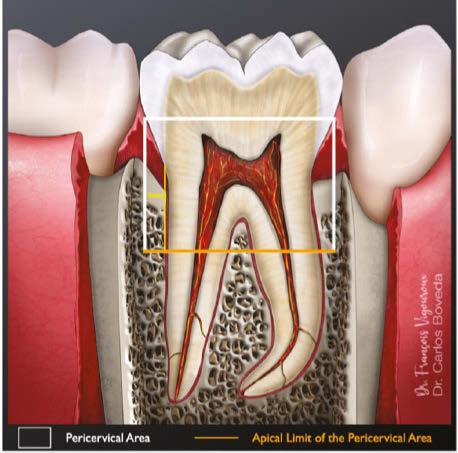

There are various factors that influence the size of such cavities, notably the anatomical location of the orifices and visualizing these orifices without tilting the mirror.12 This results in an access cavity that is widest occlusally and smallest at the level of the orifices.12,13 Hence the drawback of such access cavity design is that it requires the removal of healthy tooth structure, specifically the pericervical dentin — the dentin present 4 mm above and 6 mm below the crestal bone which helps to distribute any forces placed on the tooth (Figure 1).14 This access design, known as Traditional Endodontic Cavity (TEC) is presently being questioned, giving rise to various access designs emphasizing the preservation of this pericervical dentin.14,15

sistence of apical periodontitis. The purpose of an access cavity is to offer the clinician a proper entry into the pulpal chamber, the canal orifices, and into the canals all the way to the working length. It should allow the easy way-in and way-out of all the mechanical and chemical armamentarium during a root canal treatment.11

Traditionally, the endodontic access cavity was designed in a way that aimed to remove any obstruction in the way of reaching the canal orifices. This included the complete unroofing of the chamber, exposing all pulp horns, and obtaining a straight-line access to the apex — avoiding the need to alter visual angulation. This design also aimed at reducing the likelihood of iatrogenic errors.